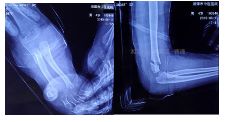

GartlandⅢ型肱骨髁上骨折患者,患肢畸形、肿胀明显。肘前方可见皱褶,典型的难复型肱骨髁上骨折。

外院拍片情况如下: